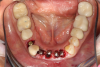

The next case follows the digital protocol for fully guided surgery and prosthetics. A CBCT radiograph, digital impression, and digital photography were the cornerstones to the success of this case. The 3D data set was electronically delivered to the dental laboratory. The data were merged and the process to develop the plan was initiated. The use of CBCT was essential in this case, particularly due to minimal space for placement of individual implants and single-unit crowns. The patient's chief concern was that she wanted to have single-unit crowns instead of fixed crown-and-bridge restorations because she was worried that she would someday find herself in an assisted-living facility; if that were to happen, she wondered, who would help floss under her bridge work? Her decision was to have single implants with individual crowns. CBCT technology is much more accurate in evaluating space maintenance and management.10 Periapicals in the past were rather close for calculating spacing; however, the CBCT identifies the buccal-lingual dimensions as well as the mesial-distal measurements. On review of the completed proposals for implant placement and provisionals, it was determined that there was sufficient spacing for implant placement to allow appropriate emergence profiles for the provisionals and then eventually the final single-unit cemented crowns. The proposal was accepted, and a 3D-printed surgical stent was fabricated, along with the PMMA provisionals (Figure 29 through Figure 35).

Fig 36. Anterior central view.

Figure 36

Fig 37. Pontic removal of No. 23 and teeth extractions.

Figure 37

Fig 38. Periodontal casualties.

Figure 38

Fig 39. Surgical guide in place.

Figure 39

Fig 40. 3 x 13-mm implants.

Figure 40